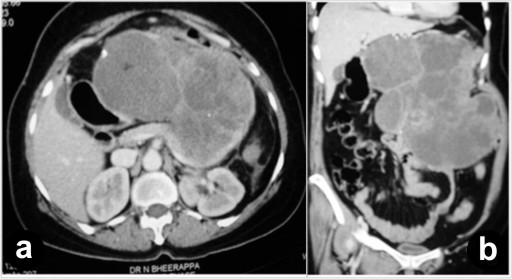

Routine laboratory investigations were within normal limits except for anemia (hemoglobin: 8 g/dL; reference range: 12-15 g/dL). A contrast-enhanced computerized tomogram of the abdomen (Figure 1) revealed a large heterogeneously enhancing mass of mixed echogenicity (mostly cystic with a few solid areas), measuring 35x30x25 cm, in the region of the body and the tail of the pancreas. The mass did not communicate with the main pancreatic duct. There were no ascites or lymphadenopathy. On magnetic resonance imaging, the mass was hypointense on T1-weighted imaging and hyperintense (cystic) on T2-weighted imaging with hemorrhagic and calcific foci (Figure 2). The possibility of a malignant cystic neoplasm of the pancreas was considered. Upper gastrointestinal endoscopy and colonoscopy showed no abnormalities. At laparotomy, a large mass was found to arise from the body and tail region of the pancreas. There was no attachment to the stomach, and the colon was stretched over the mass. There was no evidence of peritoneal dissemination. To achieve a R0 resection, a distal pancreatectomy, splenectomy and left hemicolectomy were performed.

Figure 1. Contrast-enhanced computerized tomogram of the abdomen: axial (a.) and coronal (b.) sections showing a large lobulated heterogeneously enhancing mixed echogenic lesion in the region of the body and the tail of the pancreas. |